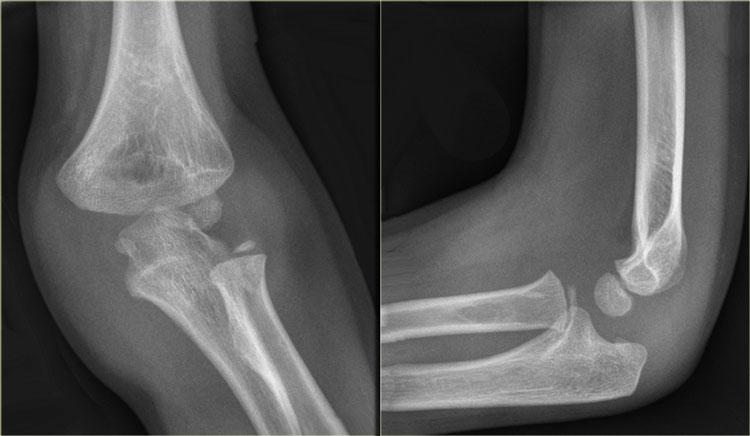

Gãy bong điểm bám mỏm trên lồng cầu trong (3).

Có 50% tỷ lệ kèm theo trật khớp khuỷu.

Khi khớp khuỷu bị trật và mỏm trên lồng cầu trong bị bong ra,

mảnh xương có thể bị kẹt vào giữa bề mặt khớp của xương cánh tay và mỏm khuỷu (hình).

Trong mọi trường hợp trật khớp, câu hỏi đầu tiên cần đặt ra là ‘mỏm trên lồng cầu trong đang ở đâu’.

Same case as above. After reduction the epicondyle returned to its normal position (not good visible due to cast) and was fixated with K-wires.

Khi nắn chỉnh khuỷu tay, mảnh vỡ có thể trở về vị trí ban đầu hoặc vẫn bị kẹt trong khớp.

Điều này có thể gây tổn thương nghiêm trọng đến bề mặt khớp.

Vì vậy, cần nghiên cứu kỹ các phim chụp sau nắn chỉnh.